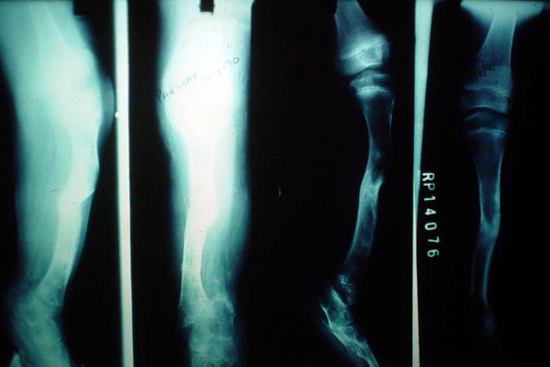

Limb Lengthening